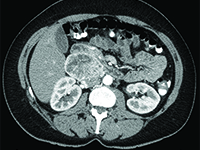

Gynecology<p>Paraganglioma(Latin: paraganglioma) is a rare, mostly benign neuroendocrine tumor originating from the paraventricular bodies of the parasympathetic and sympathetic nervous systems. The 2013 National Cancer Registry did not find any data on the incidence of this tumor in Poland [1]. The histopathological structure and symptoms of the tumor often resemble pheochromocytoma. It can be said that pheochromocytoma is a special type of chaperone tumor. Chaperones originating from the parathyroid bodies of the parasympathetic nervous system are usually located near the large vessels of the head and neck (bifurcation of the common carotid artery-the most common location) [2], while chaperones from the sympathetic nervous system chaperones occur along the sympathetic trunk located adjacent to the vertebral column, abdominal aorta and inferior vena cava [even aortic glomerulus (Zuckerkandel's organ) lying on either side of the aorta, just above its bifurcation-the most common location].</p><p>Parenomas are neoplasms of old age, with peak incidence in the 5th and 6th decades of life. In about 10% of cases, they occur familially, being part of such genetically determined syndromes as [3]:</p><p>- von Hippel-Lindau syndrome</p><p>- multiple endocrine adenocarcinoma syndrome types 2A and 2B</p><p>- Carney syndrome</p><p>Diagnosis of chaperones is not straightforward, as these tumors are rare. In cases where the tumor is hormonally active, there are symptoms associated with high levels of catecholamines in the blood (accelerated heart rate, increased blood pressure, hot flashes, headaches). When a hormonally active tumor is absent, symptoms may result from tumor growth in a specific location (dull pain in the lumbar region). Most often, however, chaperones are diagnosed incidentally in a neck or abdominal and pelvic ultrasound performed for other reasons or as an annual prophylaxis (the tumor diagnosis is then confirmed on CT).</p><p>Tumor fine-needle biopsy is unlikely to be performed due to the rich vascularization of the tumor and the associated risk of bleeding.</p><p>Because of the rarity of chaperones, there are no established diagnostic and therapeutic algorithms.</p><p>Treatment consists of surgical removal of the tumor. In cases where the location of the tumor does not allow surgical removal, radiation therapy is applicable.</p><p></p><p>Rocalization is generally very good. If the tumor is completely removed, the cure is complete.</p>